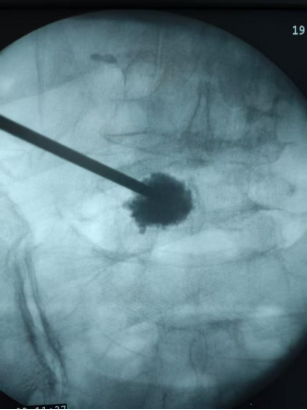

為盡快緩解李婆婆的疼痛,該院引進(jìn)的高層次人才喻林博士為李婆婆完善了相關(guān)檢查,在確診李婆婆是腰椎骨折后,喻林博士為李婆婆量身制定了治療方案,并為李婆婆實(shí)施了局麻下微創(chuàng)經(jīng)皮椎體成型術(shù),手術(shù)順利,術(shù)后李婆婆腰骶部的疼痛立即得到緩解,可以佩戴支具下床進(jìn)行活動(dòng),李婆婆對(duì)手術(shù)效果感到非常滿意。

椎體成形術(shù)是通過向骨折的椎體內(nèi)注入骨水泥,增強(qiáng)椎體的強(qiáng)度和穩(wěn)定性,以達(dá)到迅速緩解疼痛,恢復(fù)椎體的正常功能的一種微創(chuàng)治療手段。